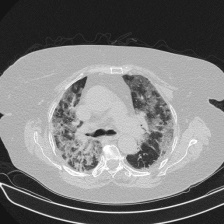

Severity Classification: Challenge to classify the involvement of lungs affected by COVID-19. This has the classes mild, moderate, severe and critical. The sampling for each of these groups can be seen in Table 1, and an example image for each of the classes is presented in Figure 3.

Figure 3: Each of the images corresponds to one of the tomography slices, with varying degrees of lung involvement by COVID-19.